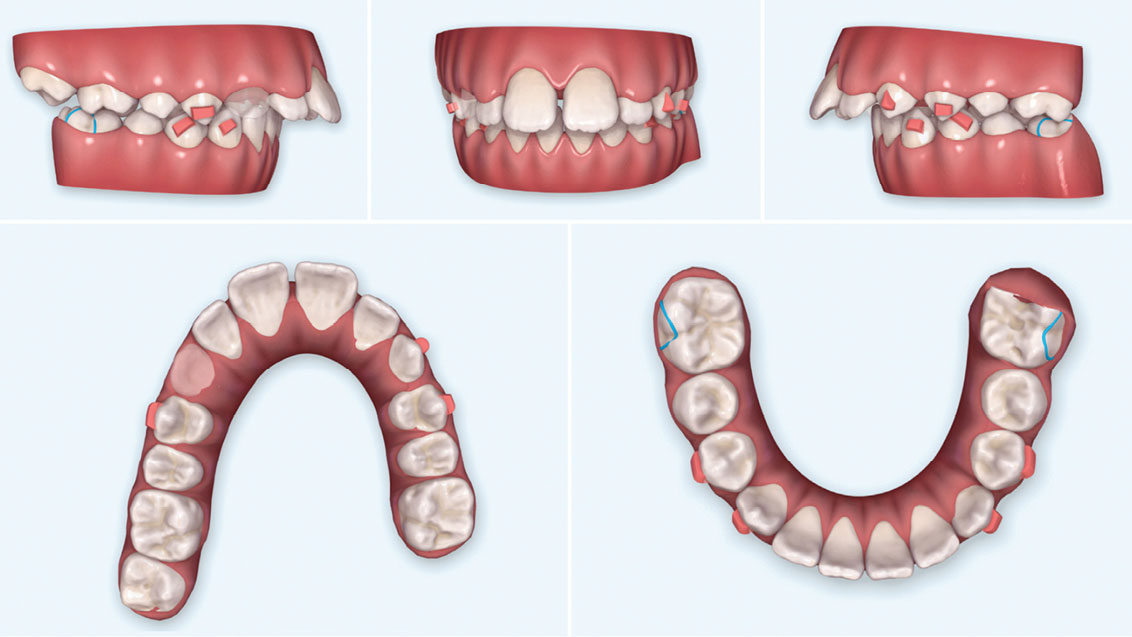

Treatment of a class II subdivision and impacted canine with Clear Carriere Motion2 and Invisalign simultaneously

This is “The most elegant way to correct class II cases” and treat an impacted canine simultaneously. I have personally met Dr. Luis Carriere and his father, Pepe (PHD in Orthodontics), at their Barcelona’s Clinic in September of 2016 to learn more about his unique approach and thinking of implementing invisalign at the same time … Read more